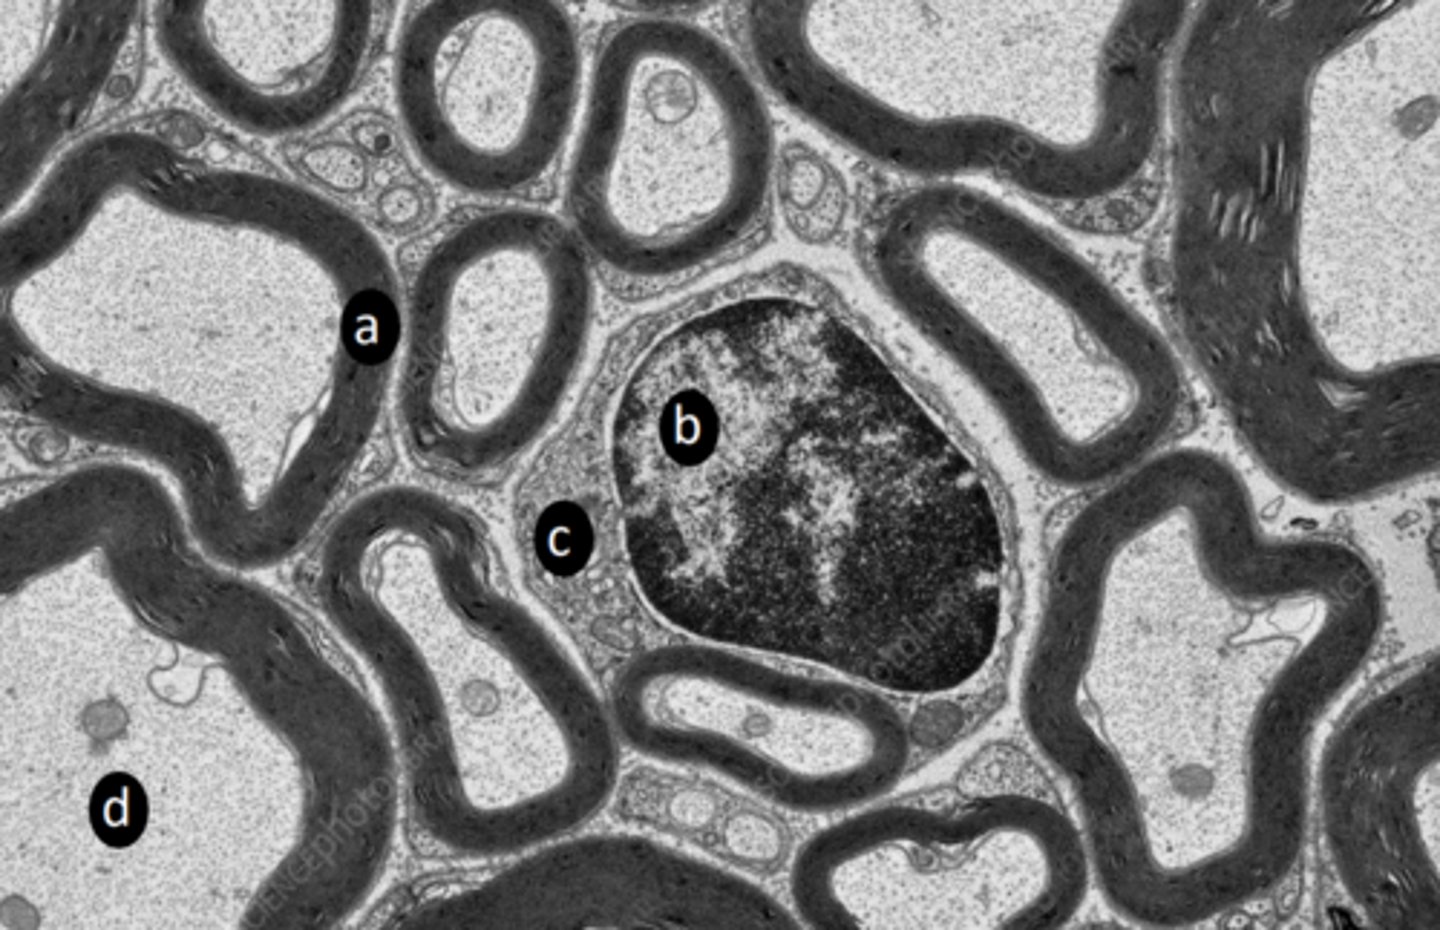

extrafusal myofibers

a: specific tissue type

intrafusal muscle fiber

b: specific tissue type

intrafusal muscle fiber (muscle spindle)

c: specific tissue type